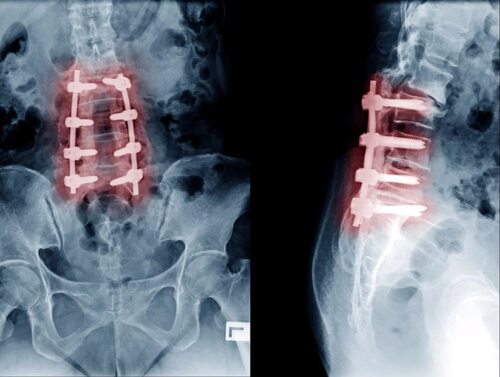

Фотографии позвоночника после операции

Здесь представлены фото позвоночника, сделанные после операции, которые позволяют оценить изменения, произошедшие в структуре и состоянии позвоночника. Некоторые фотографии показывают использование имплантатов, фиксирующих позвонки, а другие позволяют увидеть заживление ран и костной ткани.